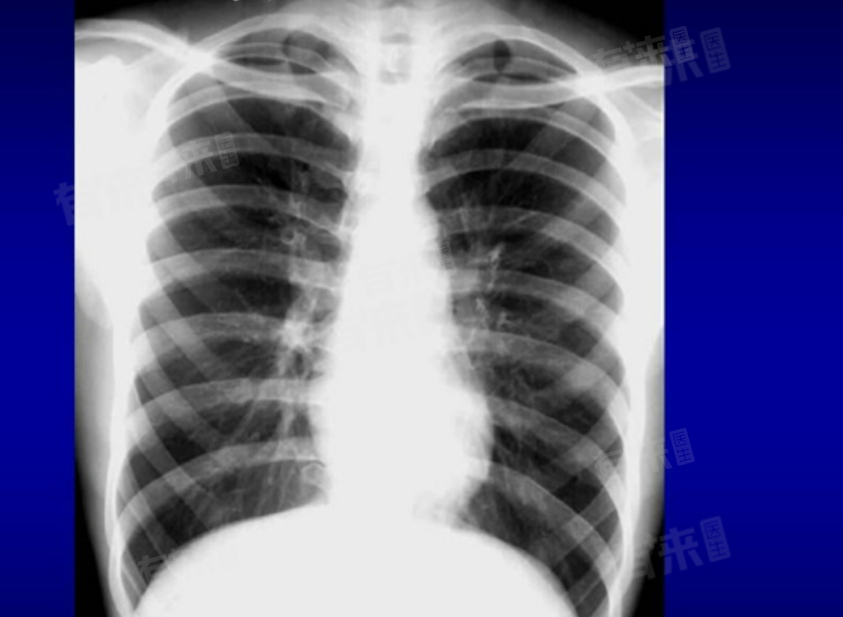

- 通常进行常规的肺部CT检查并不需要空腹,肺部CT是一种影像学检查方法,通过X射线计算机断层扫描技术,对肺部进行断层扫描,从而观察肺部结构、密度以及是否存在病变。由于肺部是呼吸系统的一部分,与消化系统没有直接关系,因此进食与否通常不会影响肺部的成像效果。